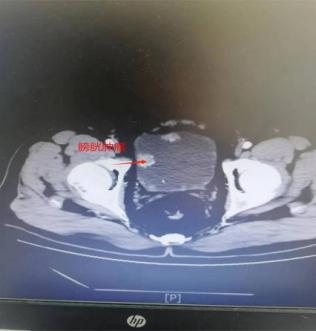

病例一:老年男性患者,74岁,因血尿1年余入院。入院完善腹部增强CT提示:考虑膀胱Ca累及前列腺,内侧髂内动脉旁淋巴结肿大,不除外淋巴结转移。膀胱镜下肿物活检病理结果提示:高级别浸润性尿路上皮癌。完善相关检查后,毕学成主任组织全科医师讨论后一致认为患者有根治性全膀胱切除指征,但患者年龄较大,合并较多基础疾病,手术风险极大。经与患者及家属详细沟通病情后建议行腹腔镜下全膀胱根治性切除术+盆腔淋巴结清扫术+双侧输尿管皮肤造瘘术。毕学成主任带领泌尿外科团队,做好术前准备,患者于8月30日在手术室全麻下,由毕学成主任主刀完成该术式,术程顺利,手术耗时3小时45分钟,出血量150ml。患者术后康复出院。

病例二:老年男性患者,61岁,因解无痛性肉眼血尿1月入院。入院完善腹部增强CT提示:考虑膀胱多发肿块,考虑膀胱恶性肿瘤。膀胱镜下肿物活检病理结果提示:浸润性低级别乳头状尿路上皮癌。毕学成主任了解病情后积极与家属及患者沟通,并制定手术治疗方案。在排除手术禁忌证后,患者于9月15日在手术室全麻下行腹腔镜下根治性全膀胱切除+盆腔淋巴结清扫术+回肠代膀胱术,手术过程顺利,耗时约5小时15分钟,出血量约100ml。患者术后康复出院。

术前部分患者CT片